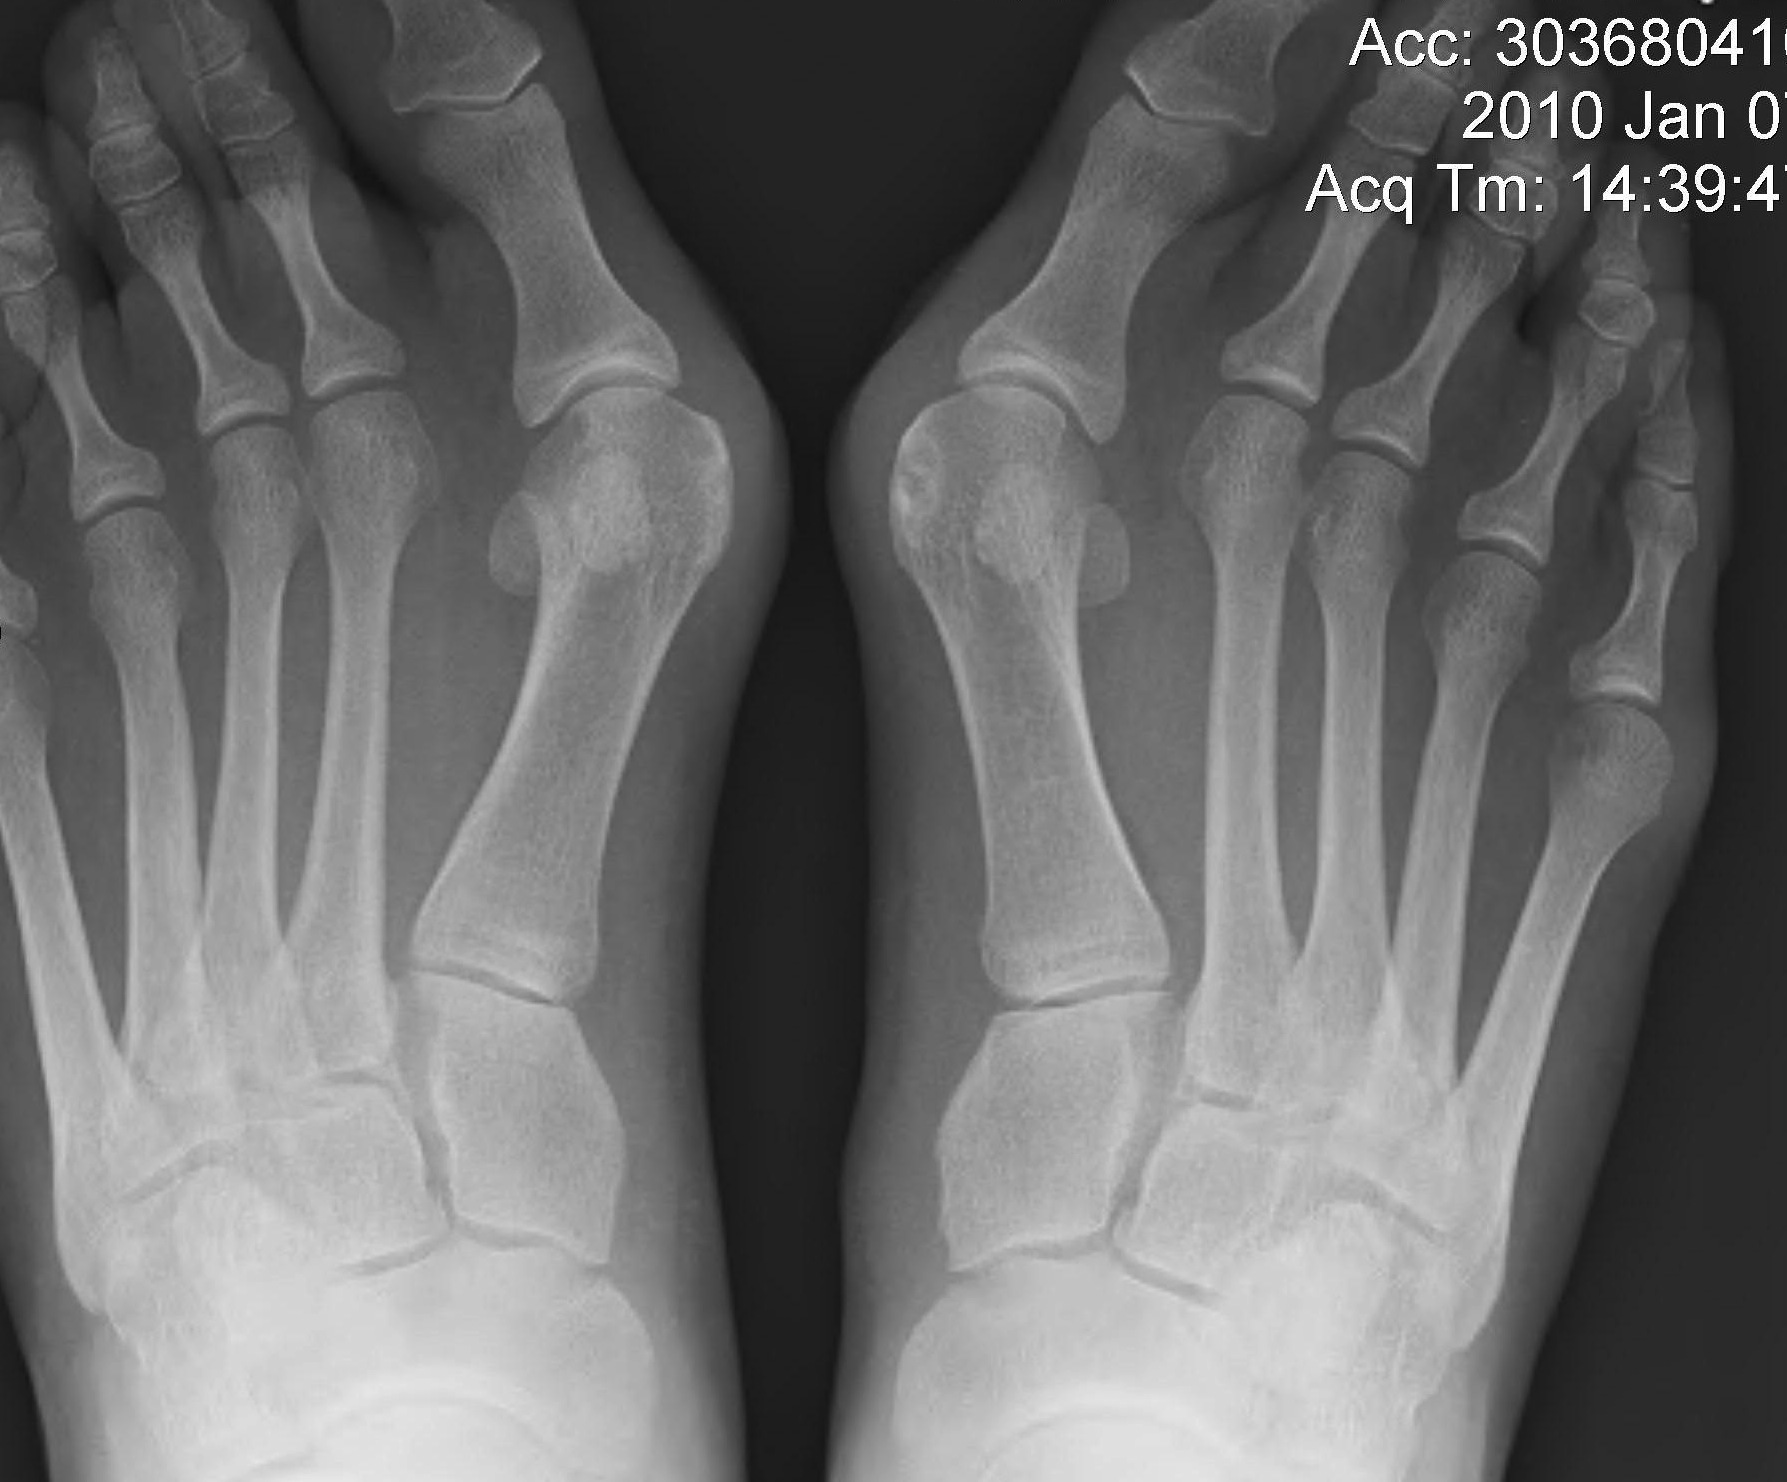

Juvenile Hallux Valgus

Pathology

Congruent joint

- 50% compared with 9% in adult HV

Metatarsus primus varus